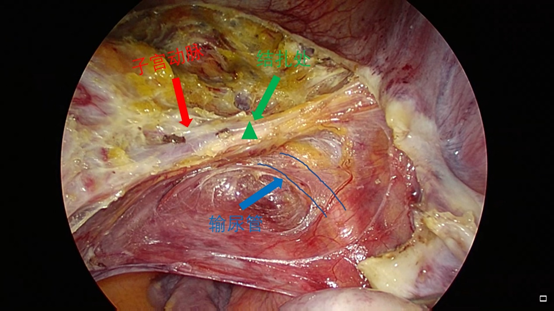

打开的层次:沿子宫血管束的前缘打开,暴露子宫血管的前缘后,再进一步分离裸化子宫血管,切忌粗暴操作,下方有静脉属支,避免损伤出血。

因肌瘤巨大,术中出血风险增大,故先行子宫动脉的临时性阻断,以减少术中出血,该视频展示了腹腔镜下经前路的子宫动脉双侧结扎操作,视频就其具体的操作予以展示。